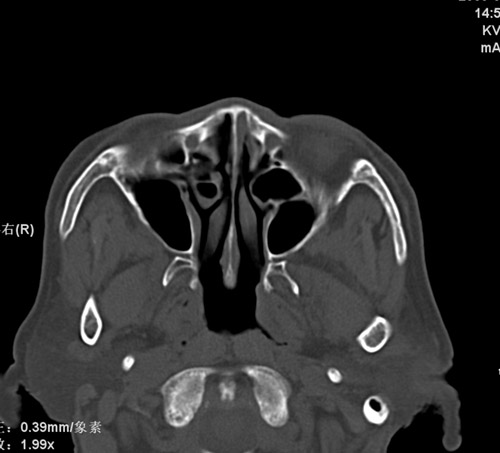

标题: CT17755:女,74 左鼻旁肿胀半年,临床以左上颌窦旁占位行CT [打印本页]

标题: CT17755:女,74 左鼻旁肿胀半年,临床以左上颌窦旁占位行CT

ct考虑鼻前庭囊肿 或鼻翼基底部慢性炎症,左上颌窦少许炎症 请指教

1)考虑左侧鼻前庭囊肿并感染。2)双侧上颌窦炎。

左侧鼻前庭囊肿并感染。双侧上颌窦炎。支持